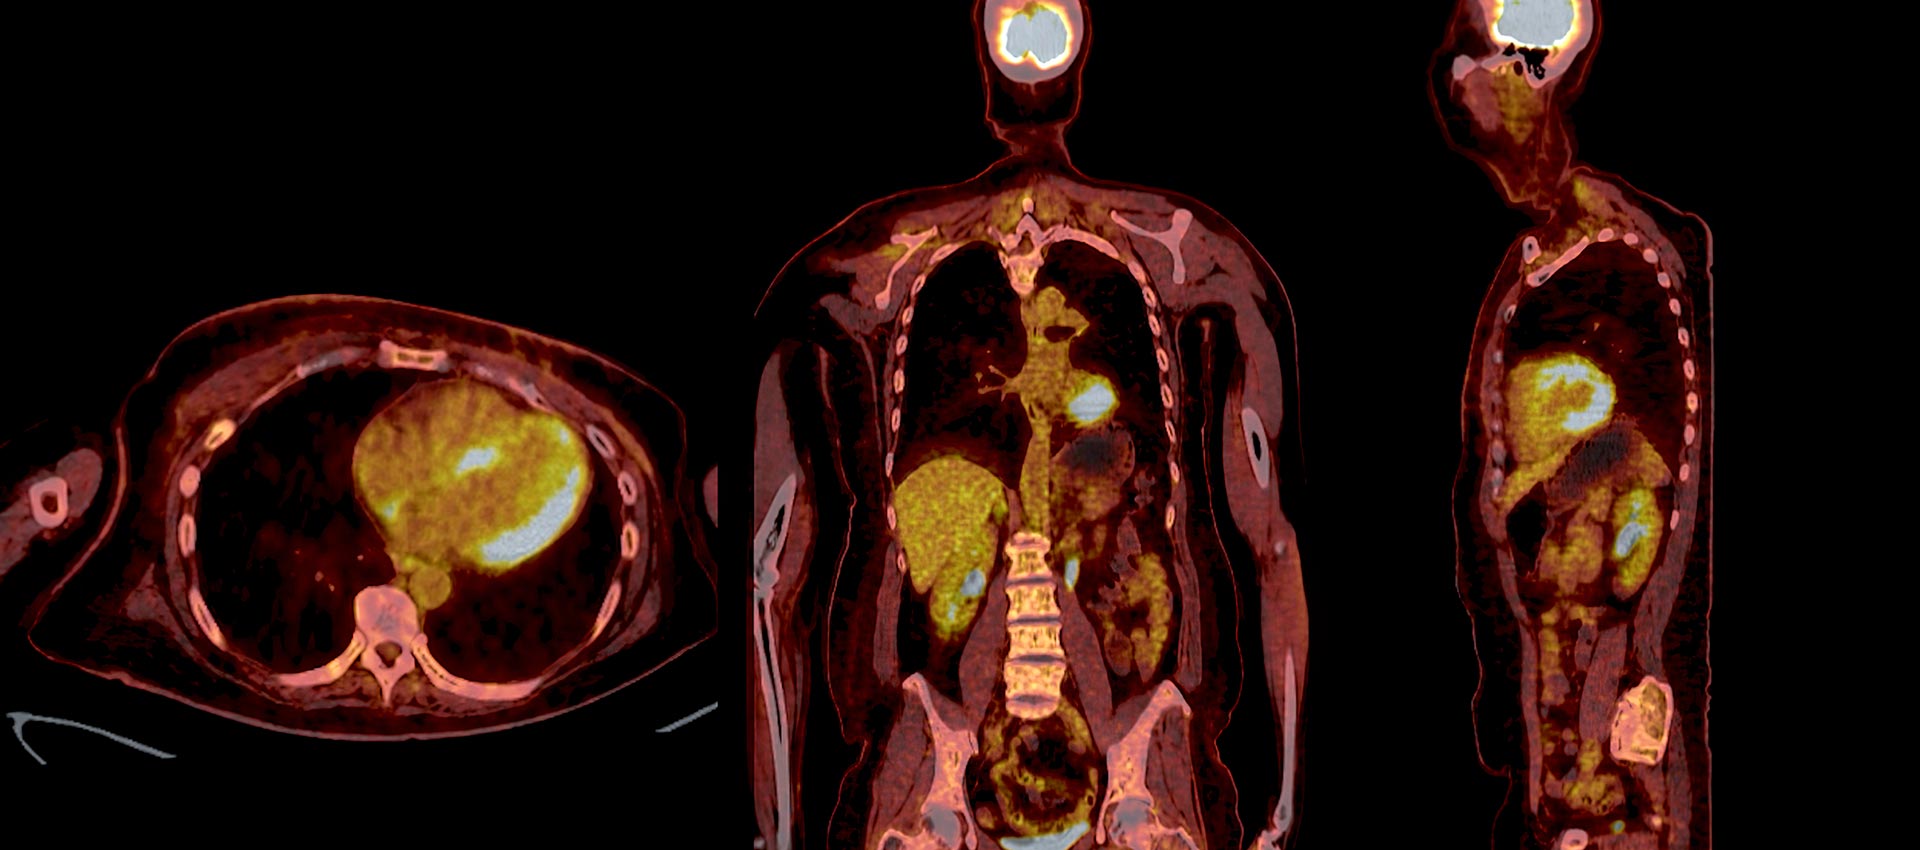

PET/CT Imaging

PET imaging is often combined with CT to provide both functional and anatomical detail in a single exam. This integration allows for more precise localization of abnormalities and supports more informed treatment planning--particularly in oncology.